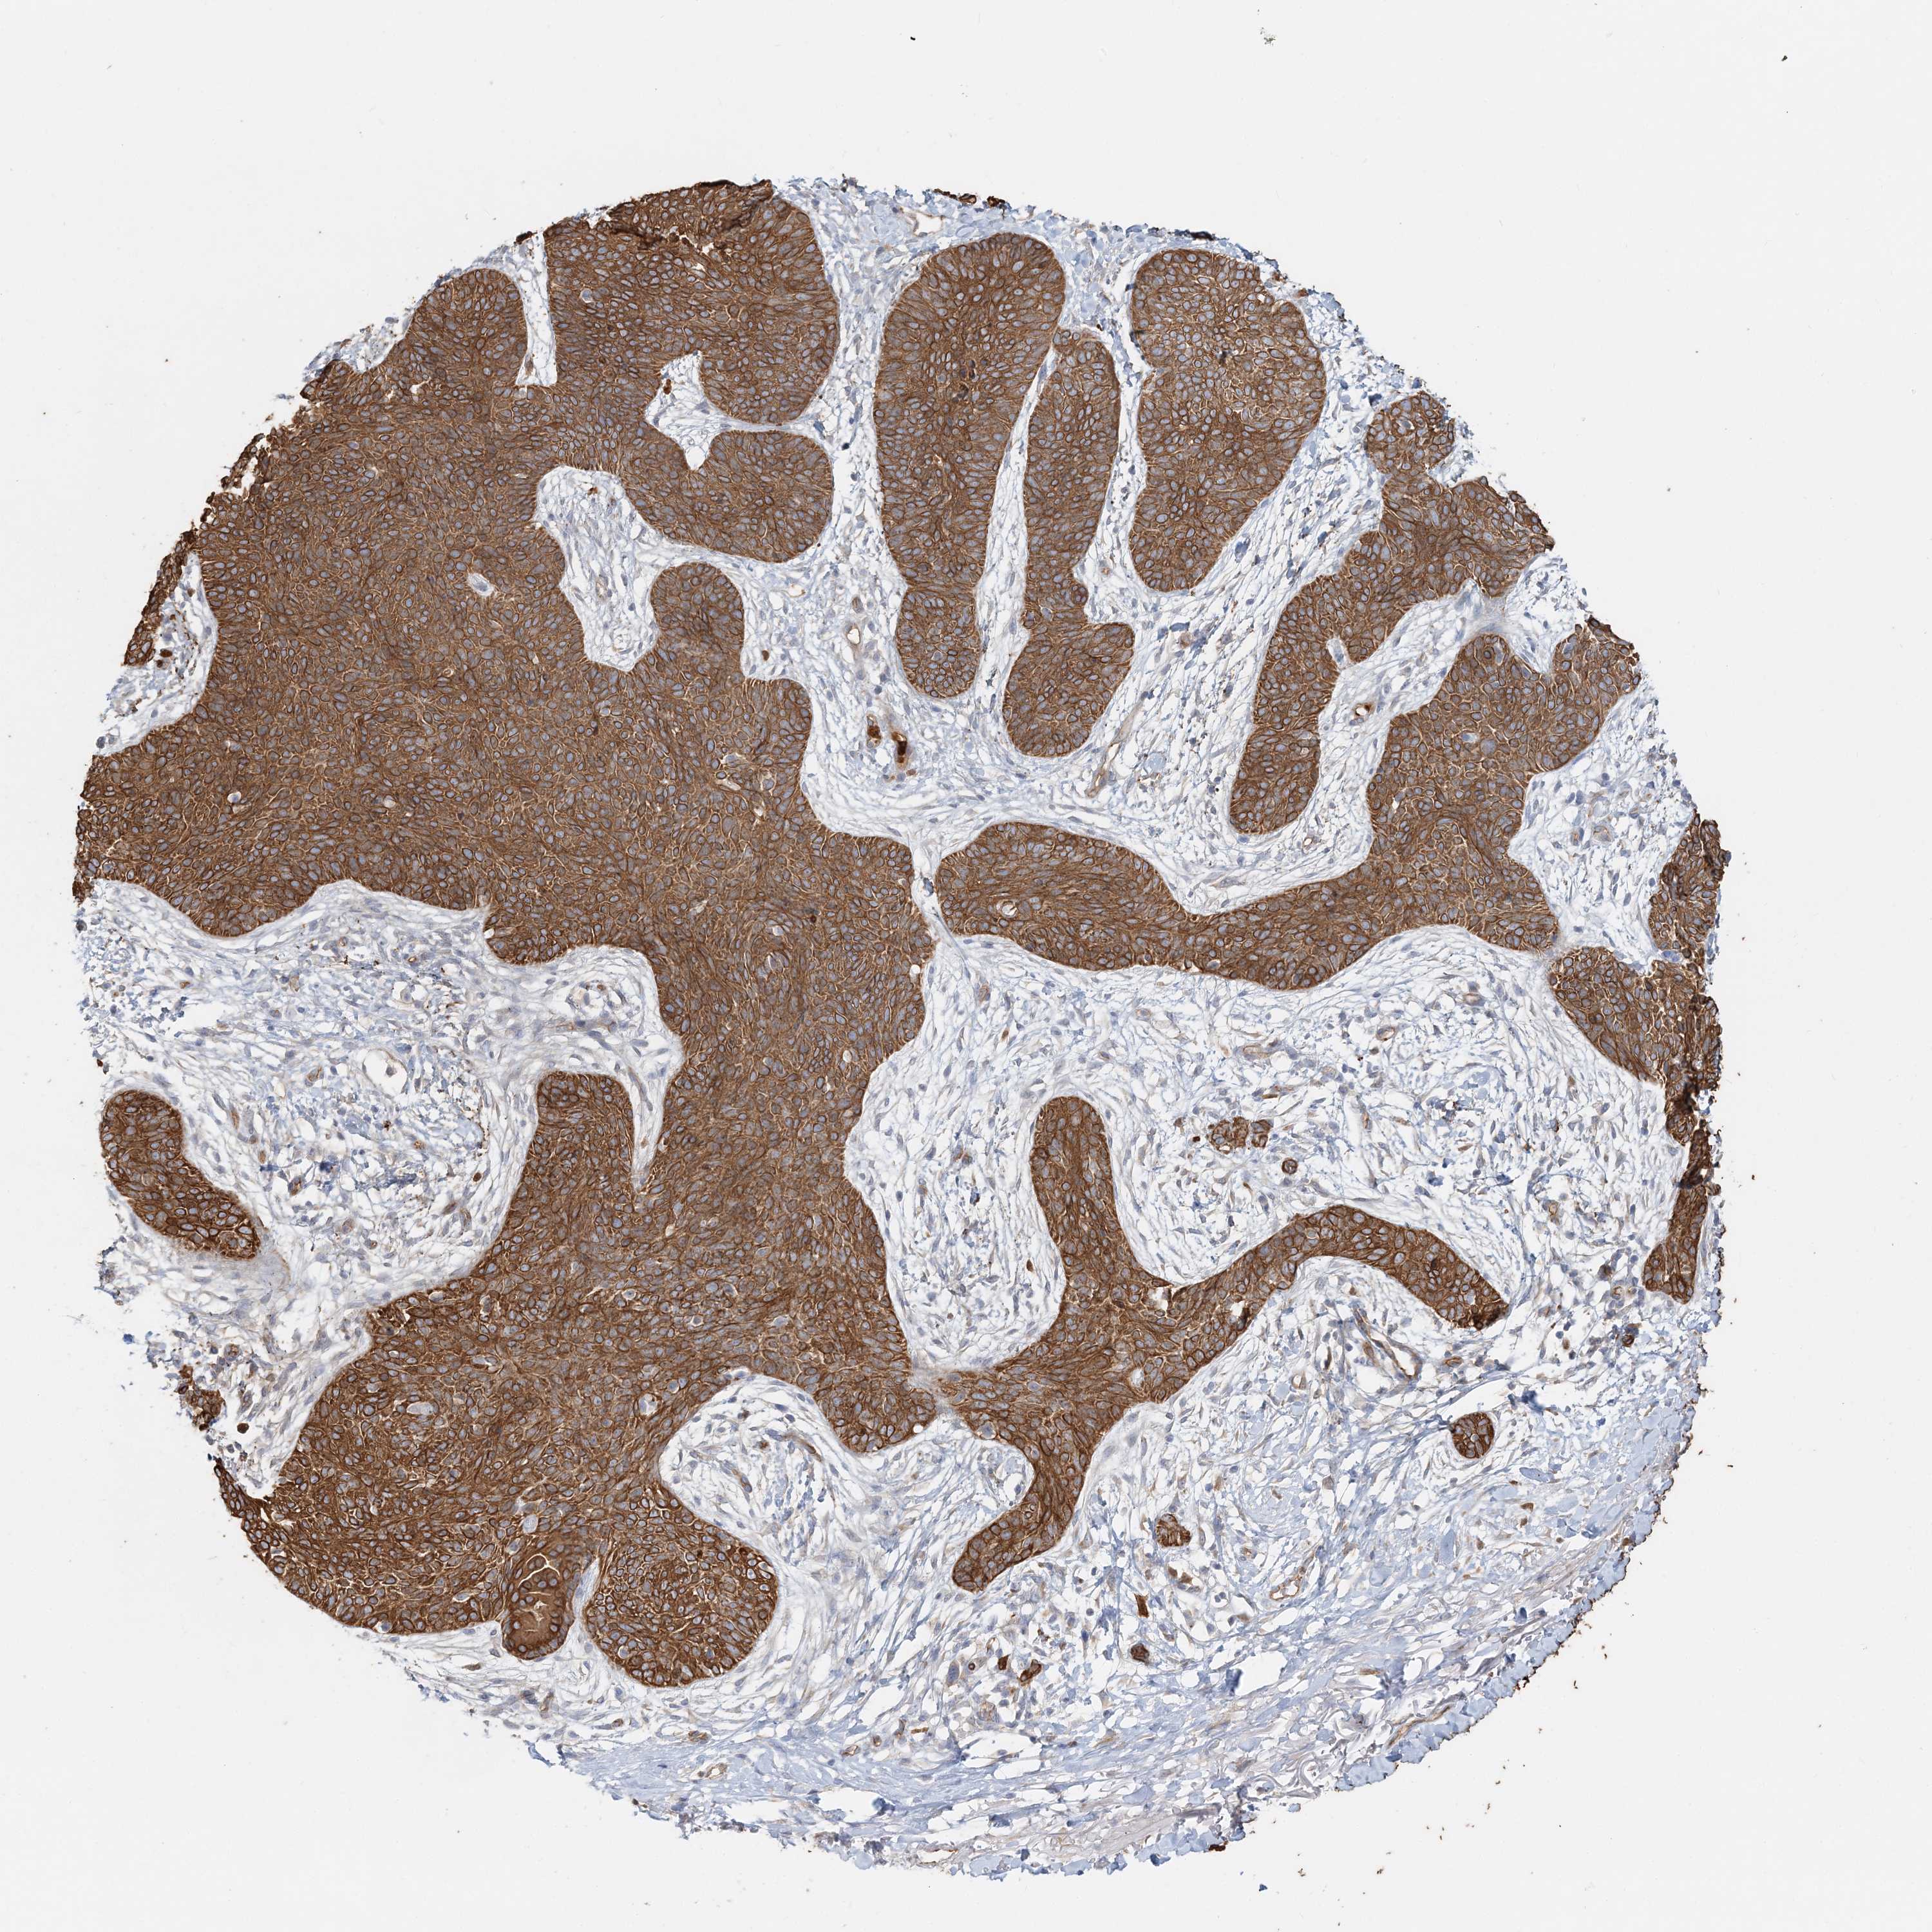

Basal cell and squamous cell cancer

SKIN CANCER - Protein expressioni

A mouse-over function shows sample information and annotation data. Click on an image to view it in a full screen mode. Samples can be filtered based on level of antibody staining by selecting one or several of the following categories: high, medium, low and not detected. The assay and annotation is described here.

Antibody stainingi

Antibody staining in the annotated cell types in the current human tissue is reported as not detected, low, medium, or high, based on conventional immunohistochemistry profiling in selected tissues. This score is based on the combination of the staining intensity and fraction of stained cells.

Each image is clickable and will lead to virtual microscopy that enables deeper exploration of all samples and also displays staining intensity scores, fraction scores and subcellular localization as well as patient and tissue information for each sample.

Antibody HPA036805

Antibody HPA036806

Staining

High

Medium

Low

Not detected

Intensity

Strong

Moderate

Weak

Negative

Quantity

>75%

75%-25%

<25%

None

Location

Nuclear

Cytoplasmic/membranous

Cytoplasmic/membranous,nuclear

Basal cell carcinoma

Squamous cell carcinoma, NOS

Squamous cell carcinoma, metastatic, NOS